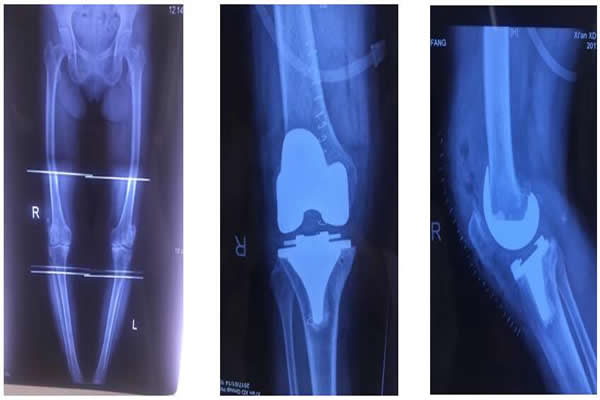

白奶奶今年72歲,雙膝關(guān)節(jié)疼痛10余年。近兩年來,雙膝疼痛加重,經(jīng)多方治療沒有任何效果,雙下肢也逐漸呈明顯的“O型腿”。近期疼痛加重,行走困難,這讓白奶奶的家人非常著急,為解除病痛,白奶奶一家慕名前來西電集團(tuán)醫(yī)院骨科就診。經(jīng)該院骨科張富軍主任詳細(xì)診查,雙膝拍片確診患有:雙膝關(guān)節(jié)骨性關(guān)節(jié)炎合并雙側(cè)內(nèi)翻屈曲畸形。為提高生活質(zhì)量,解除病痛,建議進(jìn)行同期雙膝人工關(guān)節(jié)置換手術(shù)。

術(shù)前,骨科主任張富軍、主治醫(yī)師張浩為患者制定了嚴(yán)格的治療方案,經(jīng)過2周的術(shù)前準(zhǔn)備感染指標(biāo)降至正常,于2017年1月13日在手術(shù)室、麻醉科等相關(guān)科室的周密配合下,由張富軍主任、張浩主治醫(yī)師、何鵬主治醫(yī)師、裴海波醫(yī)師為白奶奶進(jìn)行同期雙側(cè)人工膝關(guān)節(jié)表面置換手術(shù),麻醉由龐曉紅主任、劉文雄醫(yī)師擔(dān)任,手術(shù)順利,手術(shù)歷時(shí)2.5小時(shí),術(shù)后恢復(fù)滿意,術(shù)后第1天白奶奶已能下床行走,術(shù)后第6天行走出院,白奶奶對手術(shù)效果非常滿意并讓家人為骨科送來了錦旗表示感謝。